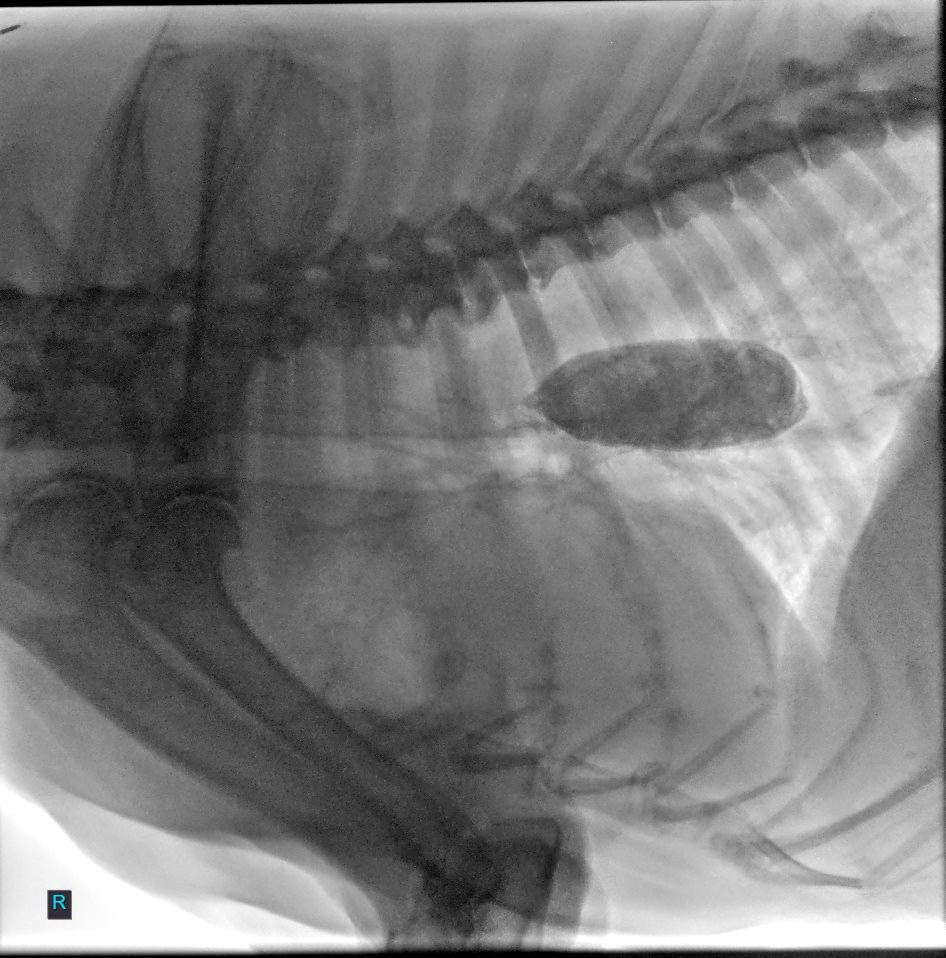

Fluoroscopy provides real-time dynamic imaging (continuous X-ray movie) of internal structures to aid with the diagnosis of conditions that may not be apparent on static radiographs. This allows for the evaluation of an in-action motion or motility of various structures to aid in the diagnosis of various dynamic diseases.

Esophageal dysmotility (video fluoroscopic swallow study).